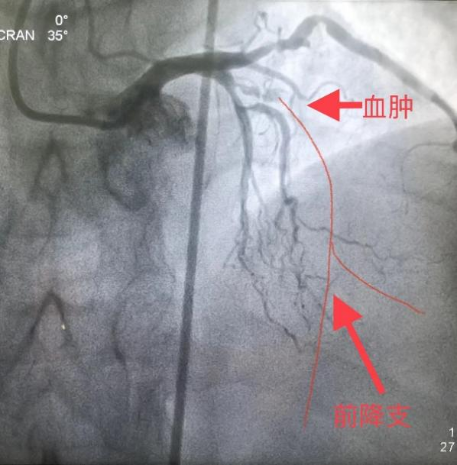

2月中旬,某患者,牛XX,男性,55岁,因冠心病、不稳定型心绞痛入住安徽省阜阳市人民医院,选择性冠状动脉造影(coronary angiography,CAG)示前降支7段和回旋支13段为CTO,右冠脉2段为重度狭窄,病变复杂,病情危重(图1)。当地医院反复尝试,历时约2小时前降支和回旋支均未能开通,遂建议患者3月后再次尝试PCI或选择CABG治疗。患者2月后慕名去武汉亚洲心脏病医院接受介入治疗,但尝试约2小时仍然未能开通前降支CTO(图2),建议患者接受CABG治疗。

图1 安徽省阜阳市人民医院手术资料